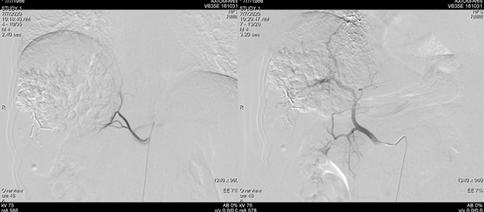

2019年2月21日以碘油5 ml+0.9%氯化钠20 ml+表阿霉素10 mg+雷替曲塞1支稀释后灌注方案行TACE治疗。后复查肝增强CT,未见明显强化,对比2019年1月病灶略缩小,初次TACE治疗达SD。

图片

图:肝增强CT(2019-02-21)

遂继续以碘油4 ml+0.9%氯化钠20 ml+吡柔比星20 mg+雷替曲塞2支方案,行第二次TACE治疗。

图:第二次TACE治疗